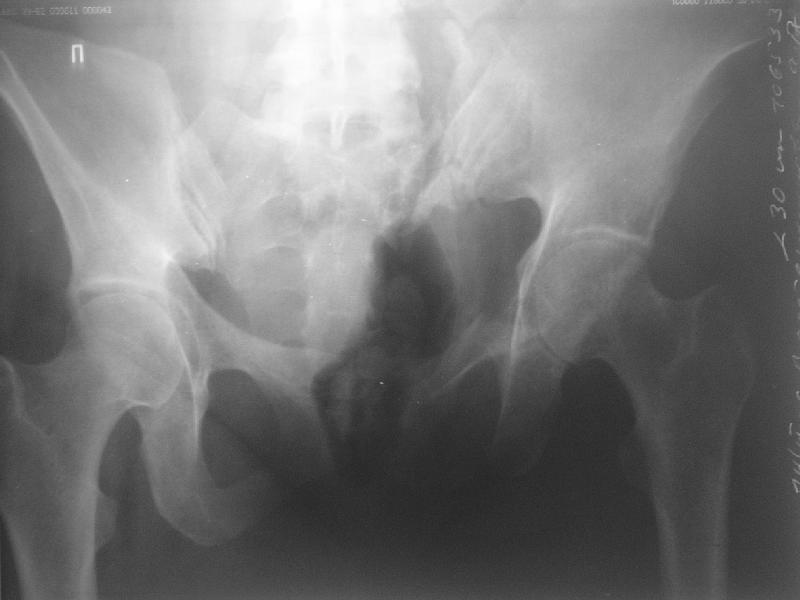

Прооперировали молодую девушку 32 лет спустя 9 мес после травмы. Имелся стойкий болевой синдром, неопороспособность левой н/конечности, моторные и сенсорные нарушения в левой голени и стопе, патологическая подвижность левой половины таза. Первым этапом закрыто в аппарате исправили деформацию ( в течении 2,5 нед). Вторым закрытое введение илиосакральных винтов в крестец (канюллированные 7,2 мм Chm) + туннелизация зоны псевдоартроза спицама Киршнера, реконструкция передних отделов таза, накостный остеосинтез . Аппарат частично демонтирпован, оставлена "передняя рама" После устранения деформации отмечен регресс неврологической симптоматики, уменьшение болевого синдрома. Интересующие вопросы: 1. Прогноз для сращения псевдоартроза крестца. 2. сроки нагрузки весом левой половины таза. Буду очень признателен за ваши мнения по этому поводу.A female 32 y.o. admitted to our unit 9 months after initial injury with pain, inability to bear weight at the left lower limb, sensor and motor disturbances in the left foot and tibia, with mobility of the left hemipelvis.At first closed reduction was performed by an external fixator within 2,5 weeks. After correction her pain decreased and some neurological progress was achieved. Now two iliosacral screws 7,2 mm were inserted, and anterior lesion was fixed by a plate. External fixator was partially unmounted, only anterior frame left in place.Images attached.How would you evaluate chances of healing of the sacrum with the current position?When would you allow weight-bearing of the left leg?THX in advance.

Мне нравится ваша закрытая репозиция девятимесячного ложного сустава, не знаю насчет туннелизации, но шурупы в 7.2 это серёзная конструкция. При стабильной фиксации крестец должен срастись, только я бы держал передний фиксатор до шести недель, костыли, а полную нагрузку разрешить через 12 недель.